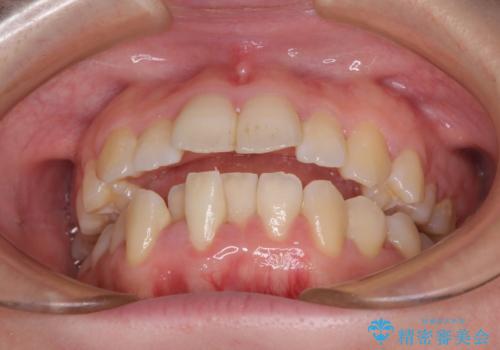

- 上下前歯の隙間と口元の出っ張った感じを気にして来院された患者様です。

上下の隙間は舌突出癖によるもので、またその癖により前歯が前方に出ている状態でした。

口元の出っ張りを改善するため、上下左右第一小臼歯4本を抜去し、ワイヤー装置にて矯正治療を行うこととしました。